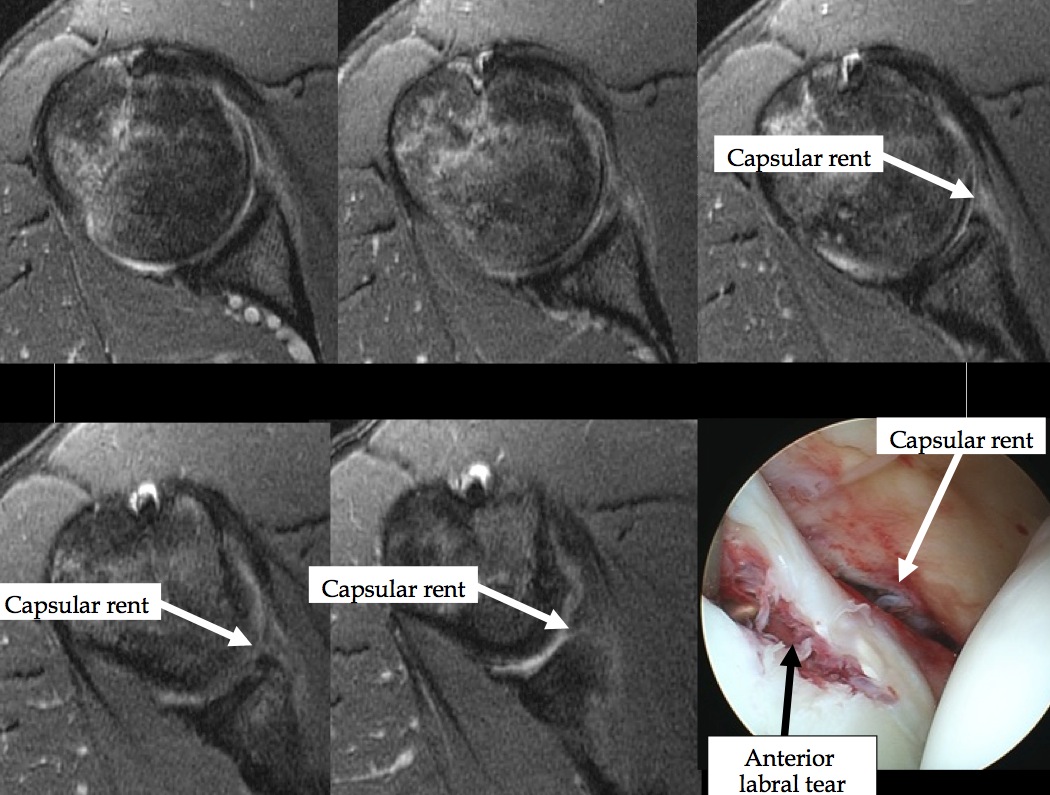

Various examples of anterior capsular injury in anterior shoulder dislocation with glenohumeral joint instability